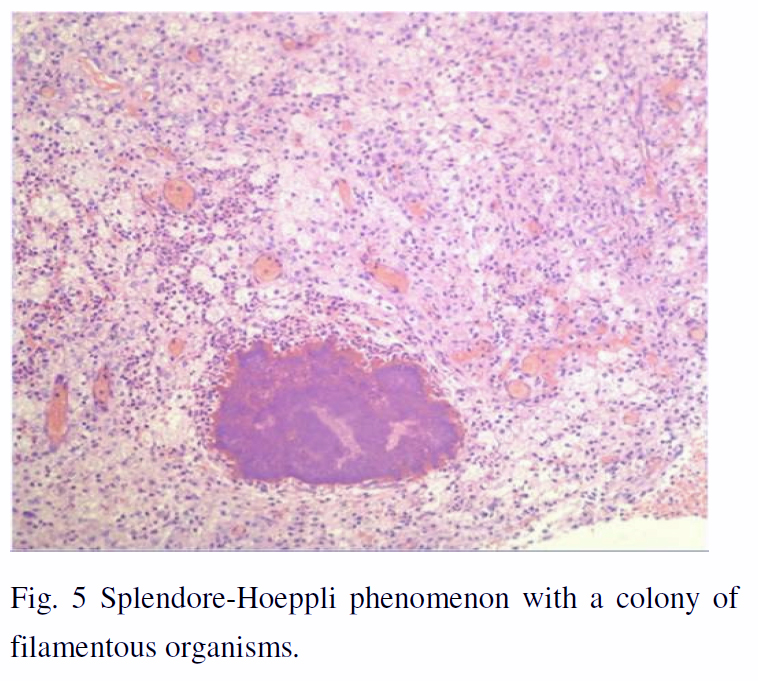

With the radiological and clinical deterioration, a CT- guided fine needle aspiration biopsy was performed which showed inconclusive inflammatory changes. Further workup revealed elevation of erythrocyte sedimentation rate (ESR) and C-reactive protein, negative ANCA and normal nasopharyngeal exam. Open lung biopsy by VATS was subsequently performed, which revealed xanthogranulomatous inflammation with Splendore-Hoeppli phenomenon. (Fig. 5)